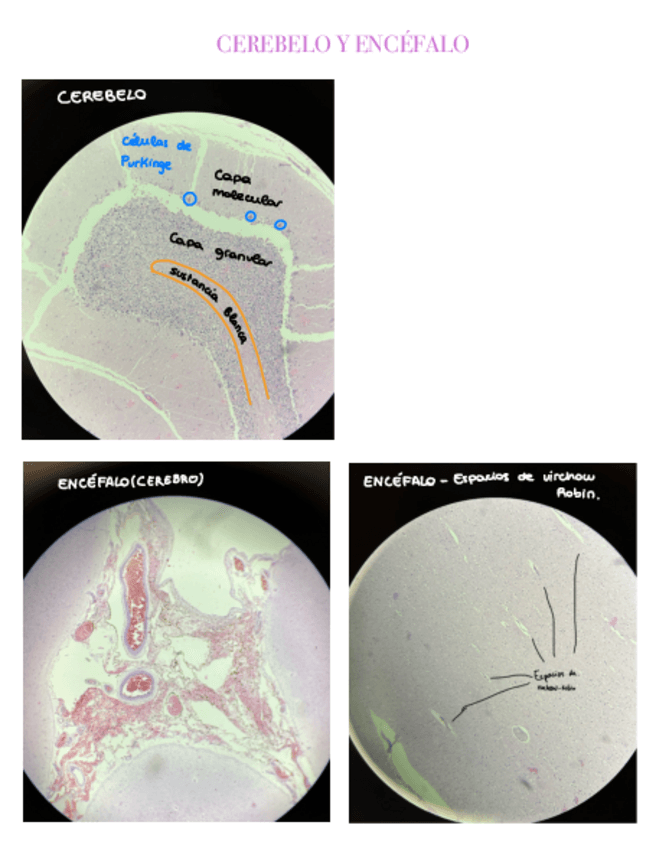

He publicado nuevos practicas de 1º Histología: Practicas-Histologia.pdf